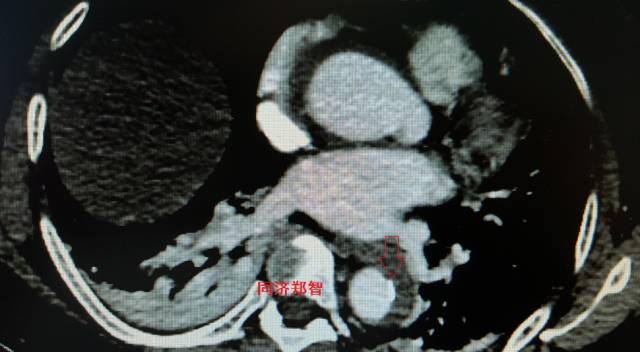

病例四

腹部平扫CT提示腹主动脉增宽,CTA证实为腹主动脉局限性夹层(红箭头所示)。